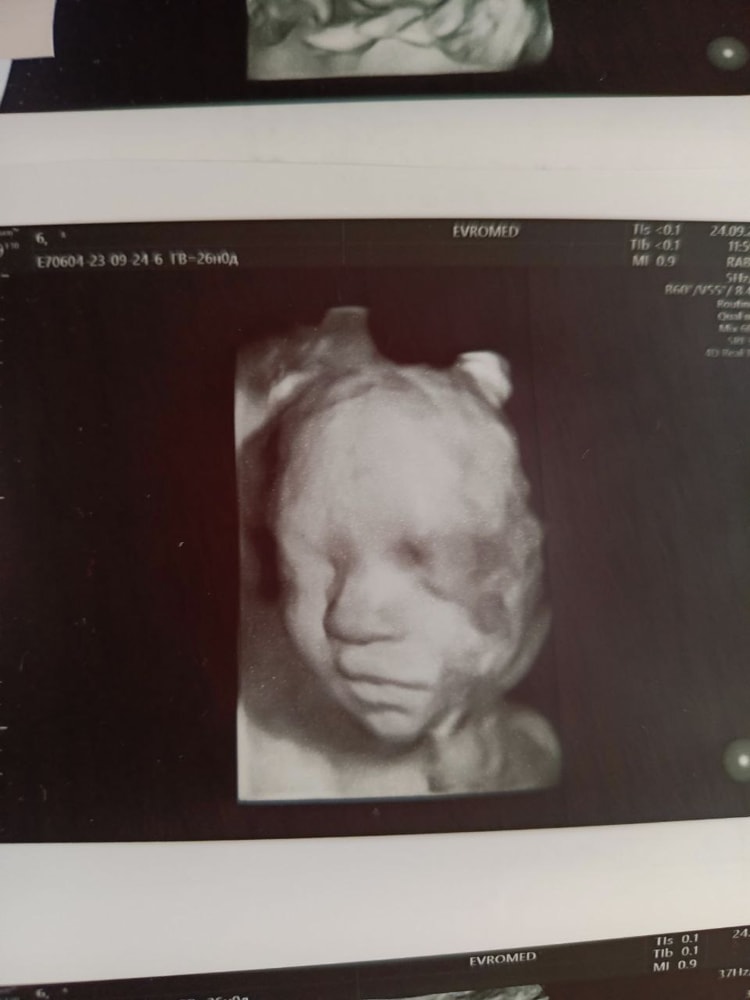

Мы с двойняшками ходили на 26-27 вроде неделе. Дочка никак не хотела лицом поворачиваться, поэтому только 2д получилось, сын прям чётенько вышел. Ходили в Евромед недалеко от дома. Место не так важно, если аппарат экспертного уровня:) Ну и от ребенка зависит получится ли фото)) Изображение Изображение Я не очень понимаю что значит 4д, потому что мы живём в трехмерном мире))

Делала в 28+4 , отлично удалось поймать личико